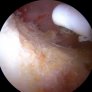

Στην παρουσίαση αυτή θα αναφερθούν τα παθολογικά προβλήματα που εμφανίζονται στην άρθρωση του ισχίου σε επαγγελματίες και ερασιτέχνες αθλητές και θα προβληθούν περιπτώσεις ασθενών από το προσωπικό αρχείο του ιατρού. Η παρουσίαση θα περιλαμβάνει την επίδειξη των απεικονιστικών εξετάσεων (ακτινολογικών, τομογραφικών και μαγνητοτομογραφικών), καθώς επίσης και εικόνες των παθολογικών βλαβών κατά τη διάρκεια αρθροσκόπησης του ισχίου.